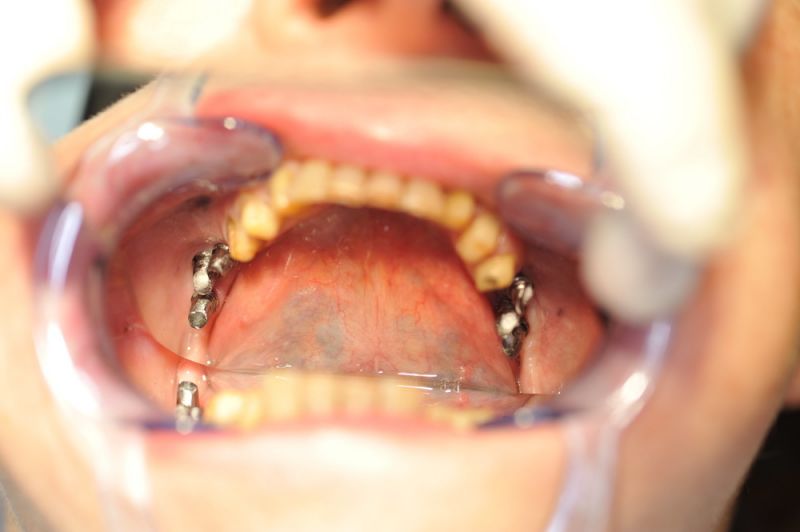

4. Notwendigkeit die Mundhygienefähigkeit der Arbeit auch unter sehr beengten Verhältnissen zu schaffen, um der Arbeit eine günstige Prognose mitzugeben.

1. Notwendigkeit eines professionellen regelmäßigen Recalls, alle drei Monate

2. Notwendigkeit der Intrerdentalraumhygiene. Zwischen den Zähnen einmal pro Tag. Zwischen den Implantataufbauten zweimal pro Tag.